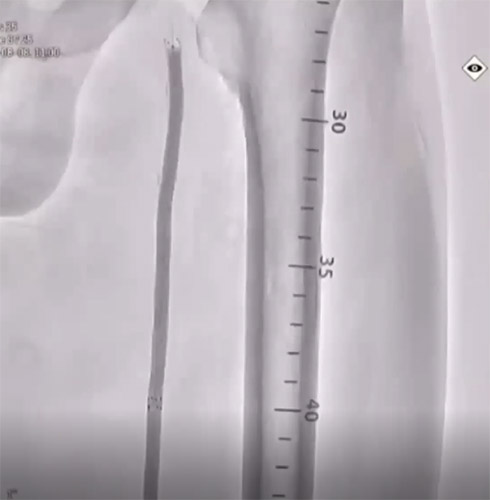

主訴は跛行(Rutherford分類3)の方で ABI検査を実施したところ0.62と低値。リスクファクターとして糖尿病(DM)、高血圧(HT)、脂質異常症(DL)が認められた。今回の標的病変は左大腿動脈(Lt. SFA CTO)【図1・図2】であり、アプローチ部位はTAI(Trans ankle intervention)にて施行することとした。

BKについてはATAは開存しており、PTAが途中から閉塞していることを確認した。【図3】